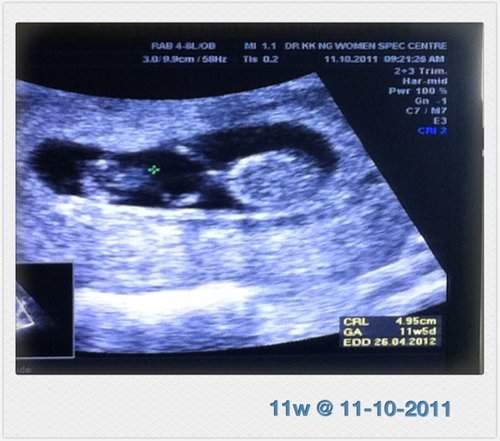

週期 : 11w (超音波顯示11w5d)

身長 : 4.95cm

心跳 : 150